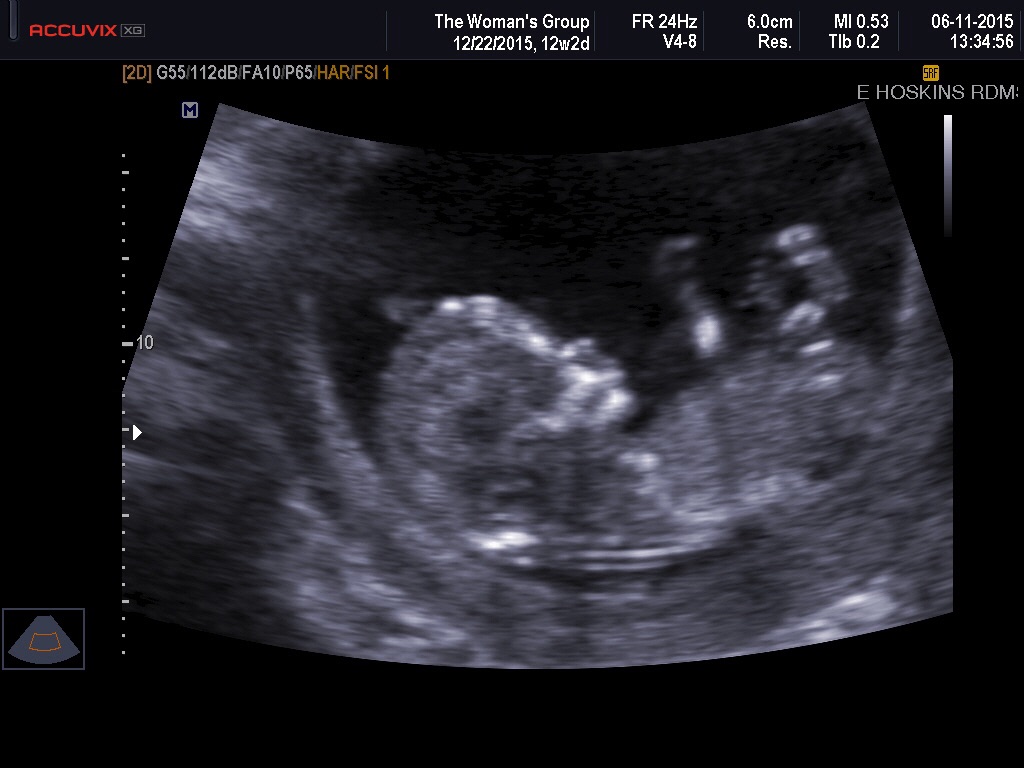

Without knowing the results of my blood test, the US went well! for the first time I got to see our little peanut, measuring at 12w2d right on target. My DH was soo happy because he hadn't been able to hear the heartbeat on the doppler at my last OB appt like I did. Warm fuzzies!!

12+2 week NT scan today! Heartbeat was 169! I just always keep preparing myself for terrible news, it's such a relief to be done with the appointment. So thankful that the appointment went well. My heart hurts for others on here that did not have good news. 16 weeks will be checking the cervical length, which I have had significant anxiety about.